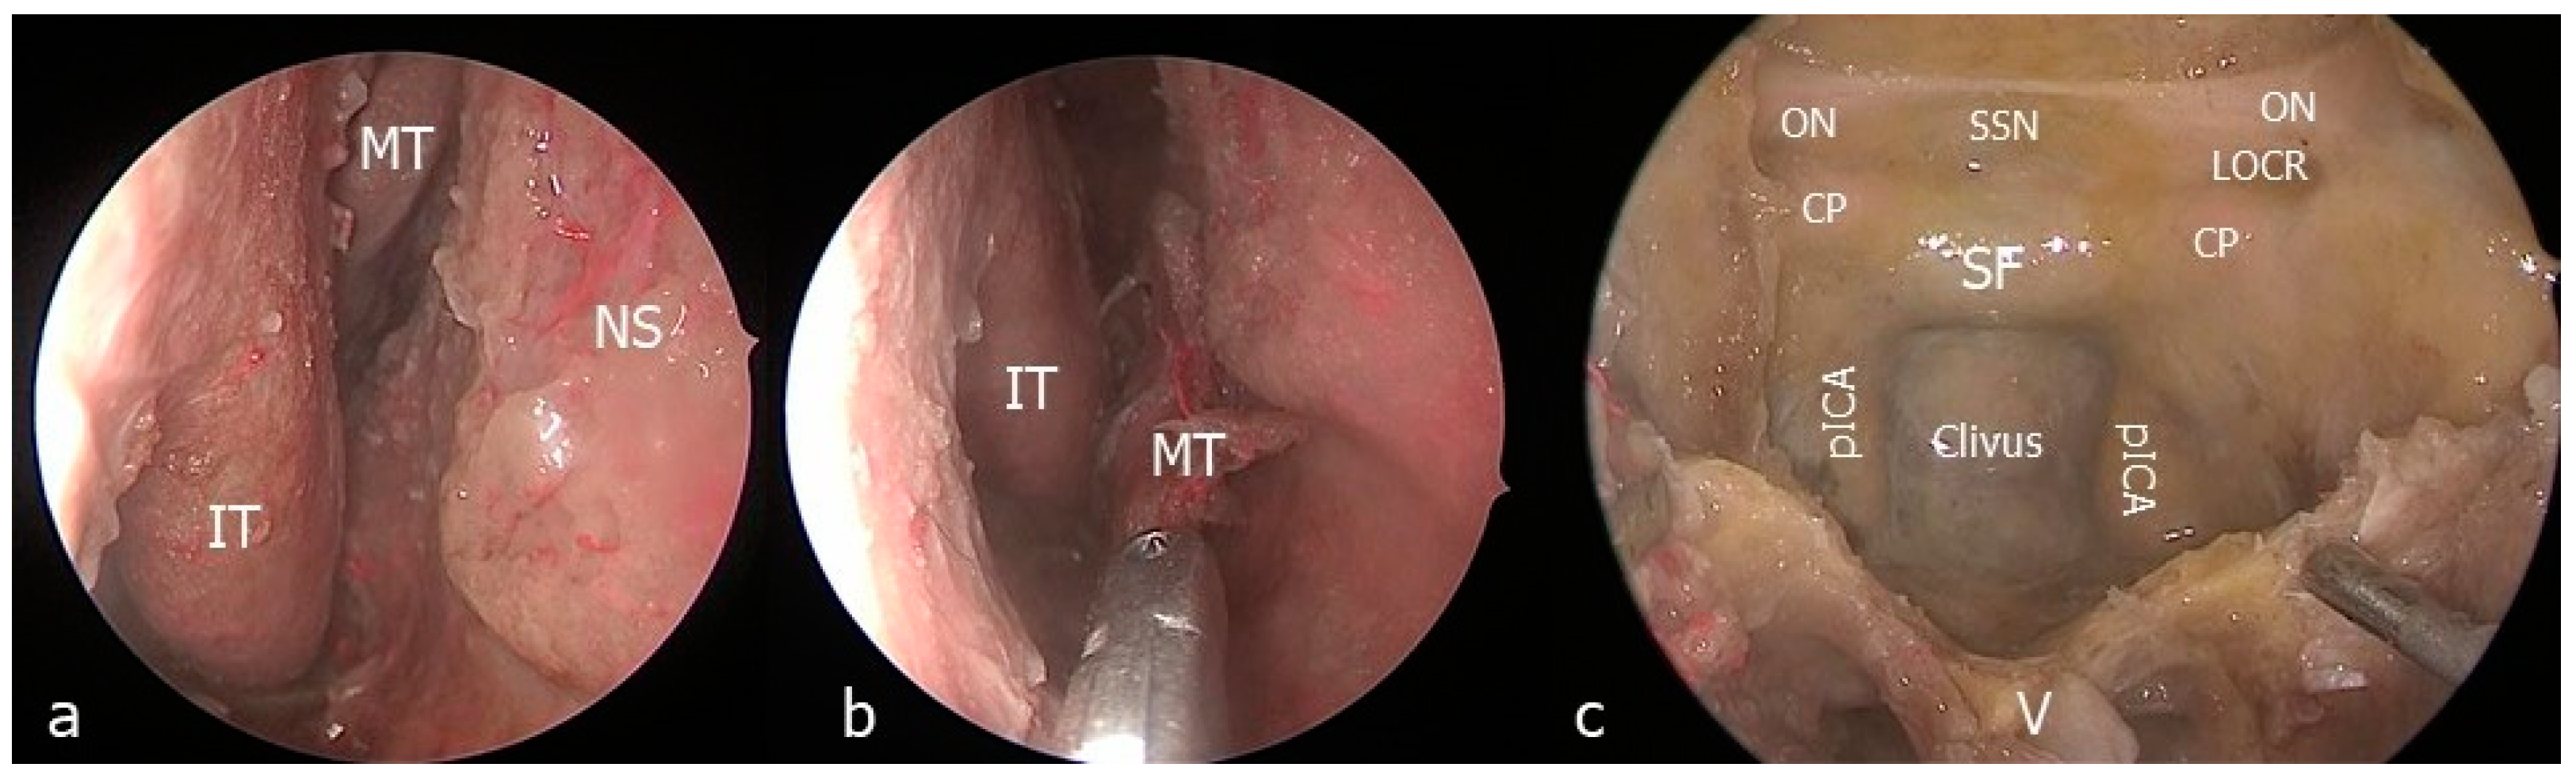

2.2. Surgical Technique

- The nasal step

- The clival step

- The maxillary step

- The petrosal step